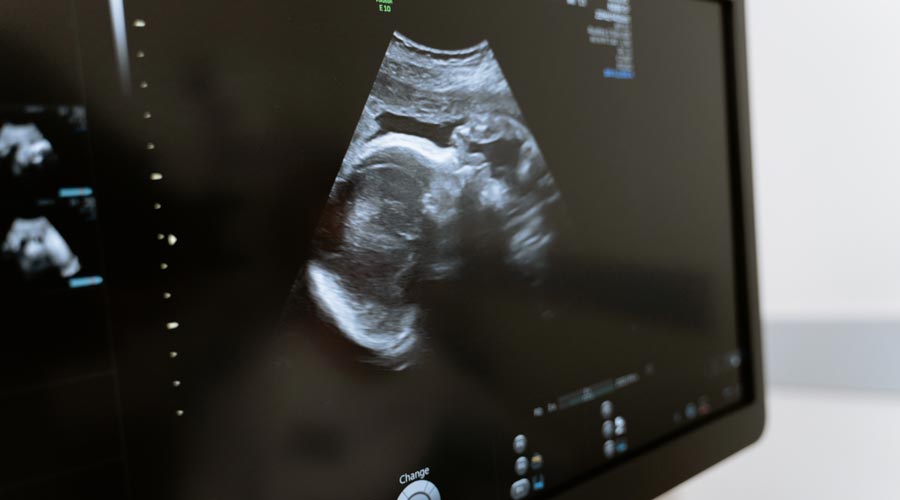

Erfahre hier alles über die Reaktionen deines Körpers in der Schwangerschaft.